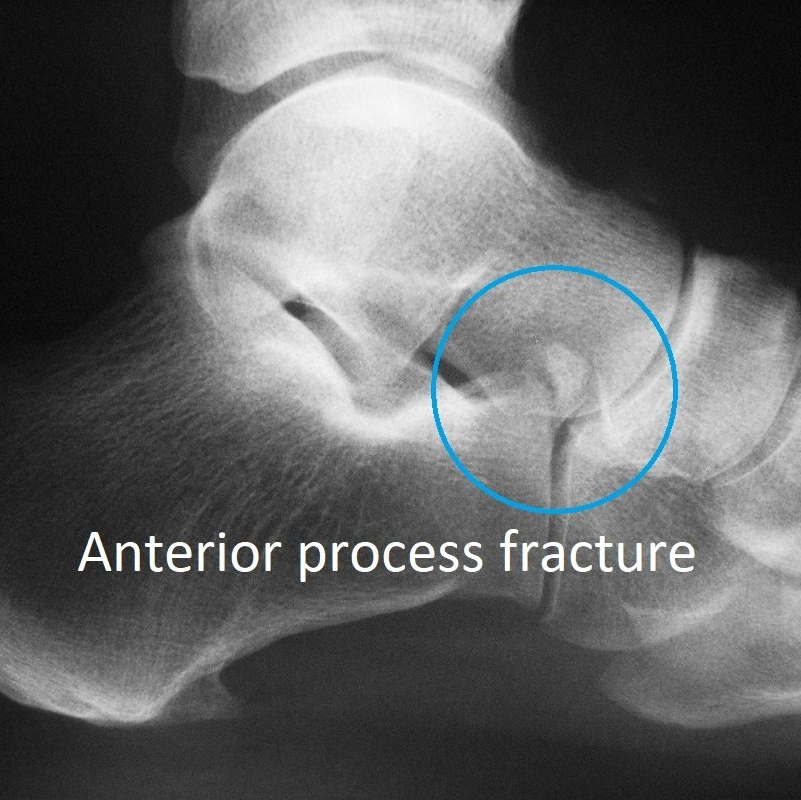

avulsion fractures of the anterior process occur with twisting injuries (see Why is my ankle sprain not getting better?).

- X-rays

- CT scan.

These imaging investigations show which part of the calcaneus is broken, and how badly. This determines both the need for surgery and the risk of long-term complications. Severe injuries can lead to hindfoot osteo-arthritis.